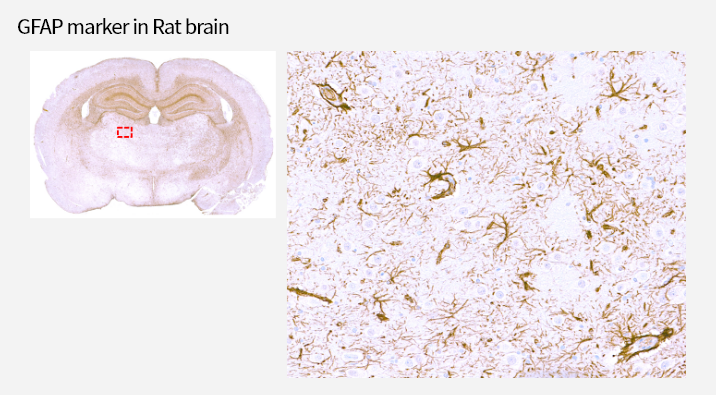

IHC stain

IHC Antibody test

면역조직화학염색 (IHC)